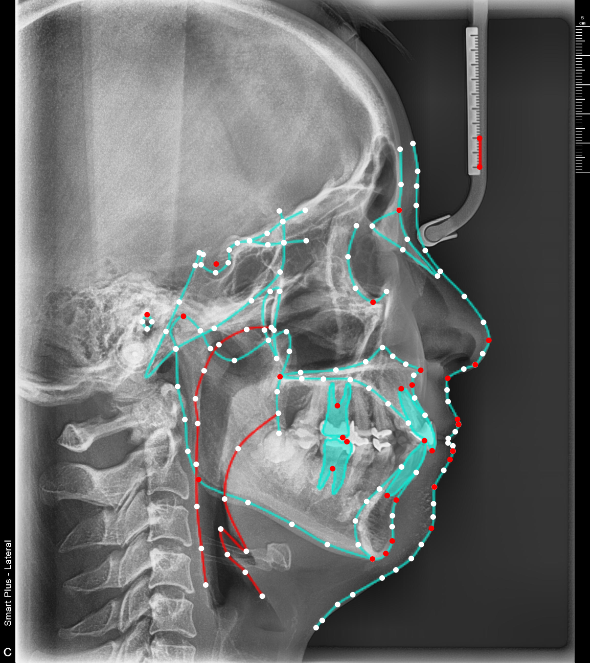

歯並びだけでなく、CBCTおよびセファロ分析で骨格や顎関節、骨の厚みまで含めて分析することで、無理のない、安全性を考えた治療計画を立てることができます。

無理な移動や後戻りリスクを防ぐ